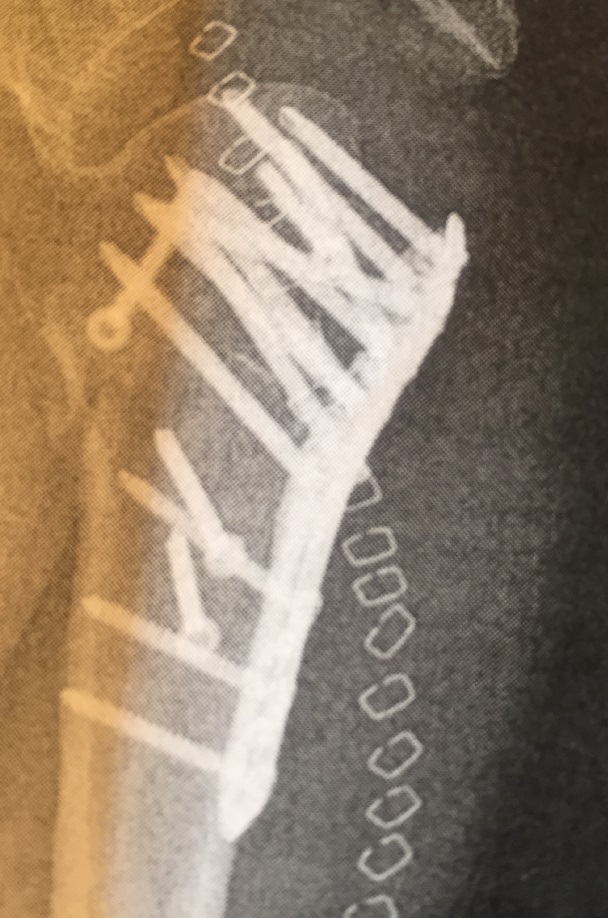

Was du in der Schulter hattest habe ich noch im Sprunggelenk.![]()

Ich finde die zolligen selbstschneidenen Spax sehen irgendwie minder aus (ist der Schraubenkopf auch eine Mischung aus Inbus & Torx in Specialgröße?)... Die elox grünen Titans machen mehr her - blau fand ich jedoch schöner

Ansonsten ist getackert besser als genähnt, geht jedoch nicht immer... Ziept auch nicht so beim entfernen![]()